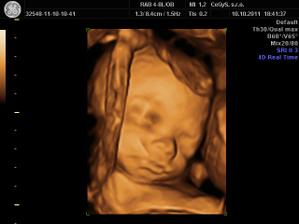

10.10 - 3D u Dr. Hlavacika v CeGys, vysoka spokojnost, mily pristup, krasne fotecky, sme na nasu Misku hrdi - je krasna uz teraz!!! V 25tt vazi o trosku viac ako by mala a to 725g...